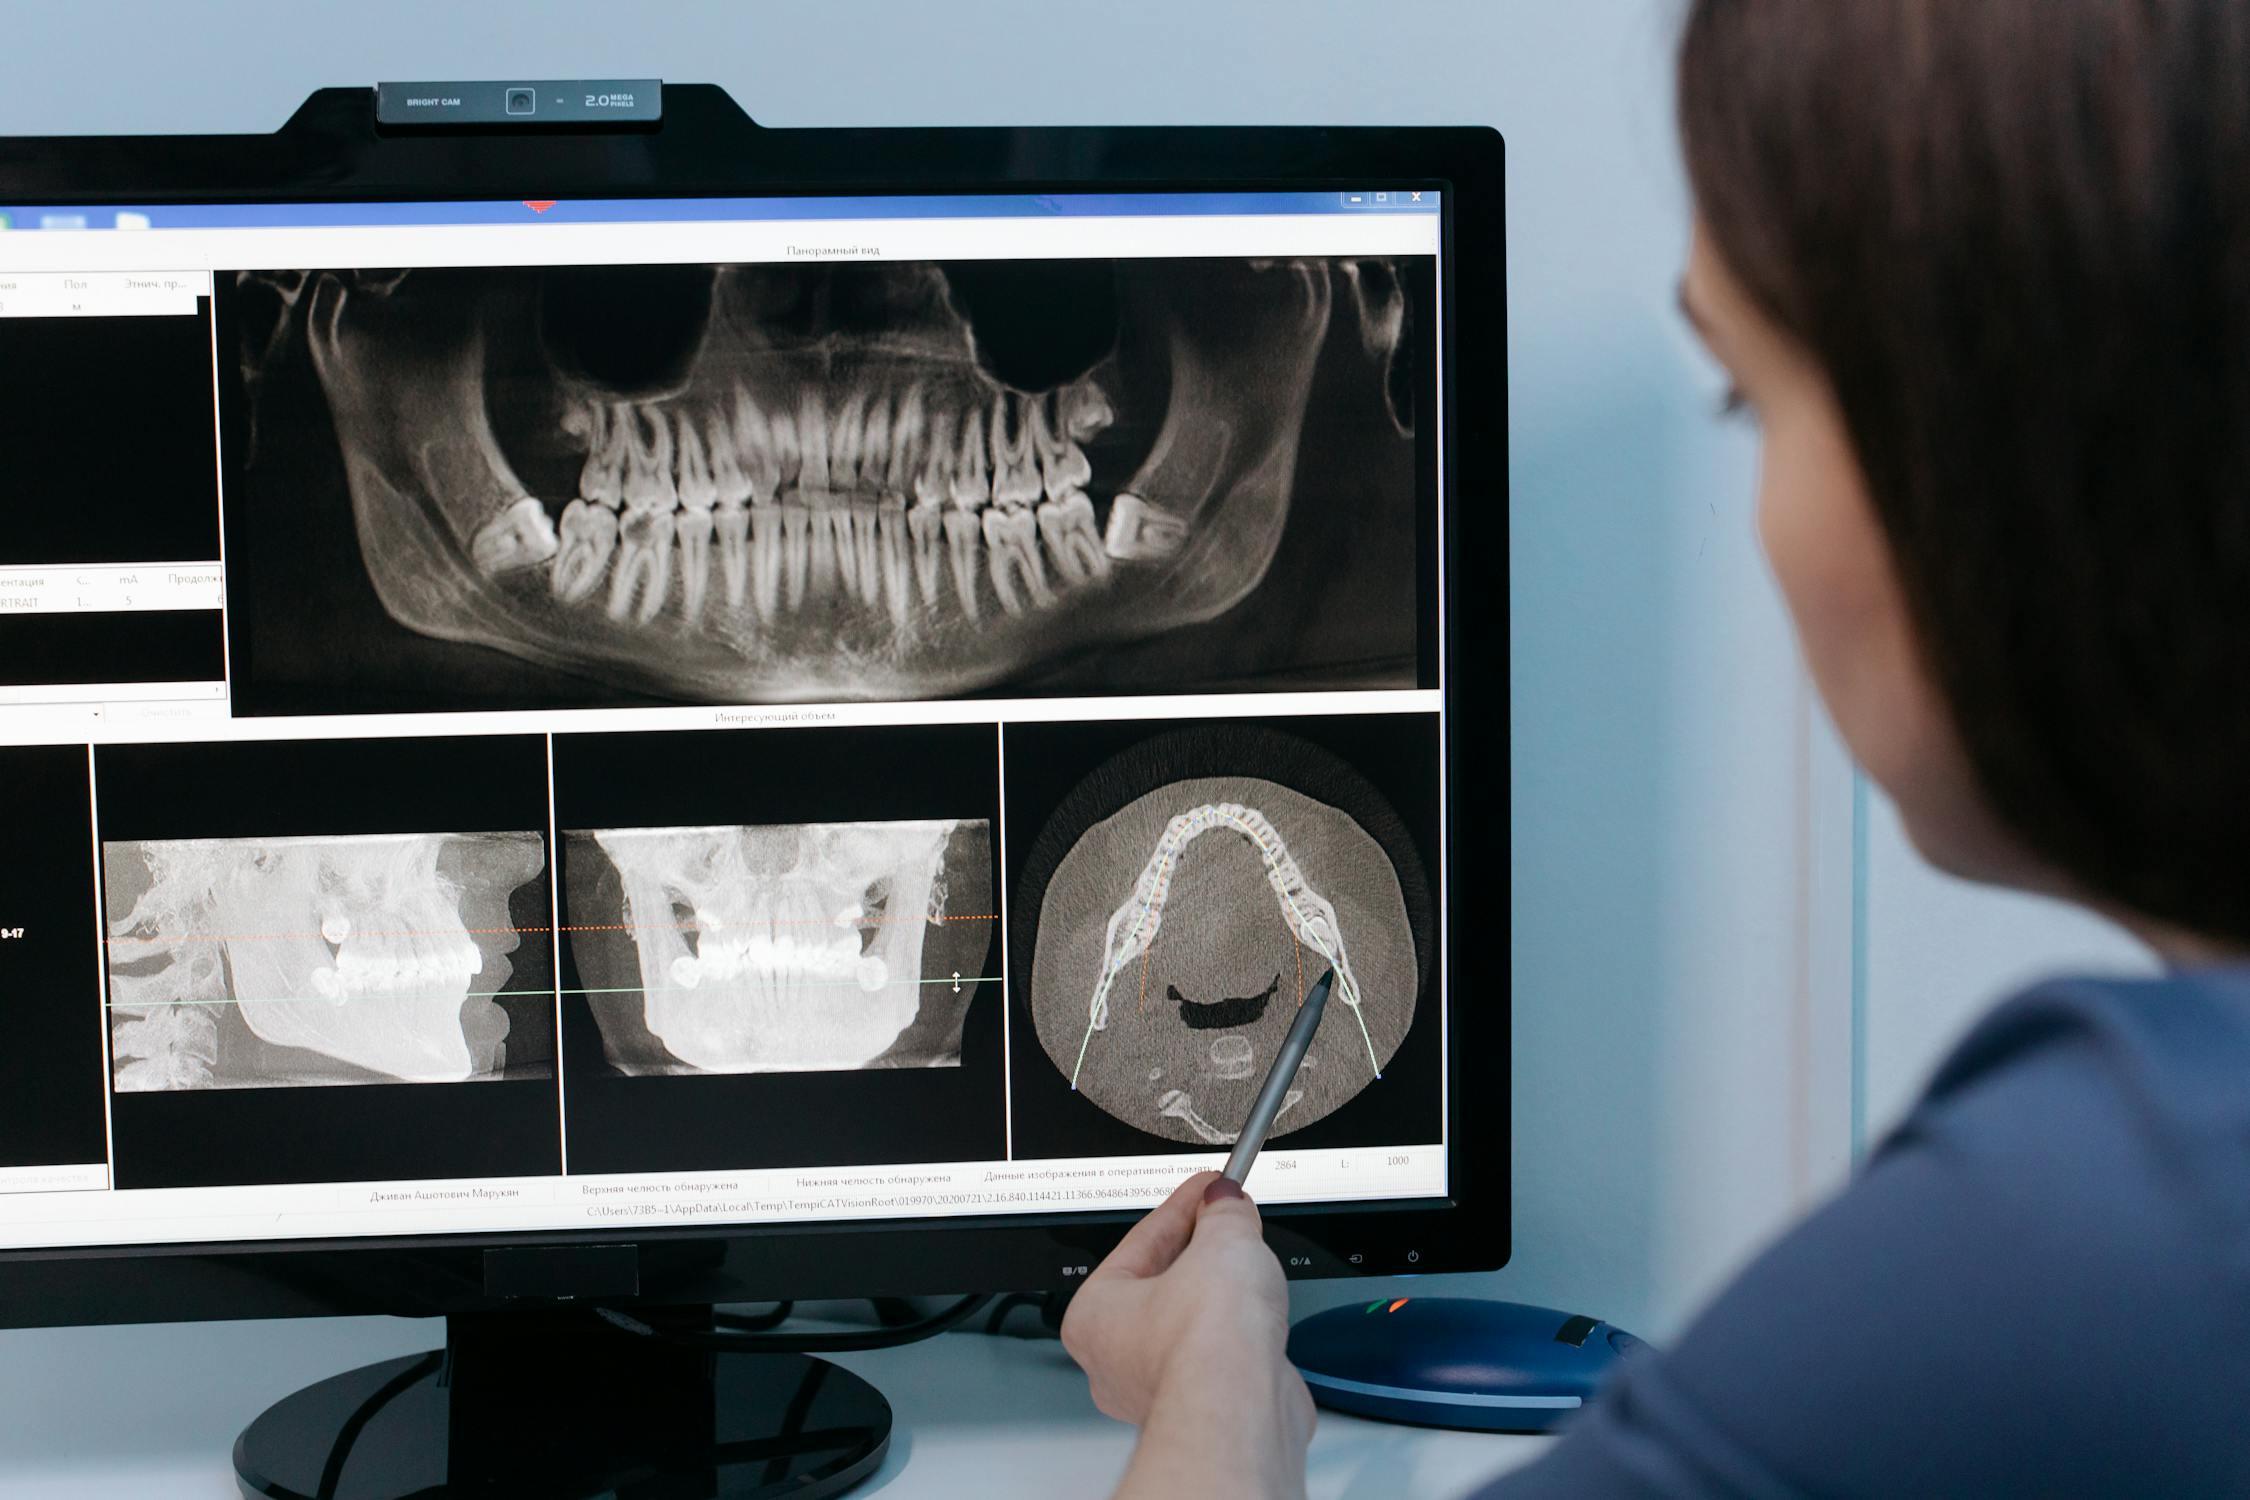

오늘은 턱관절의 기능 이상으로 인해 발생하는 문제로, 턱통증, 귀뚜라미 소리, 턱관절의 제한 등으로 일상생활에서도 상당한 불편을 끼칠 수 있는 턱관절장애에 대하여 알아보겠습니다.

턱관절은 모든 턱운동의 중심축으로 작용하며 턱 근육과 인대에 의해 지지 되는데, 이때 턱관절 사이에 있는 디스크는 뼈와 뼈 사이의 쿠션 역할을 하게 되며 이러한 근육과 인대, 디스크, 턱뼈가 함께 어우러져 개구(입 벌리기)와, 저작(씹는 행위), 말하기, 삼키기 등의 복합적인 활동을 담당하게 되는데, 여러 요인에 의해 이러한 턱관절 기능에 이상이 생긴 것을 턱관절 장애 또는 악관절 장애라고 합니다.

3. 턱관절장애의 증상

턱관절 장애의 대표적인 증상으로 통증을 들 수 있는데, 음식을 씹거나 하품할 때 양쪽 귀 앞의 아래턱뼈와 저작 근육에 통증을 느끼게 되며 또한 입을 열 때마다 턱 관절에서 소리가 나며(관절 잡음), 입과 턱의 움직임이 제한되어 집니다(하악운동 제한).

4. 턱관절장애의 치료

턱관절의 증상에 따라 적절한 교합치료, 약물치료, 물리치료, 운동요법, 행동요법 등을 시행하게 됩니다.